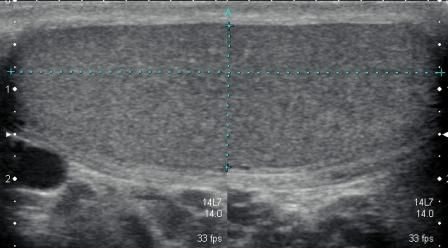

探头纵向扫查睾丸

正常睾丸矢状面图像